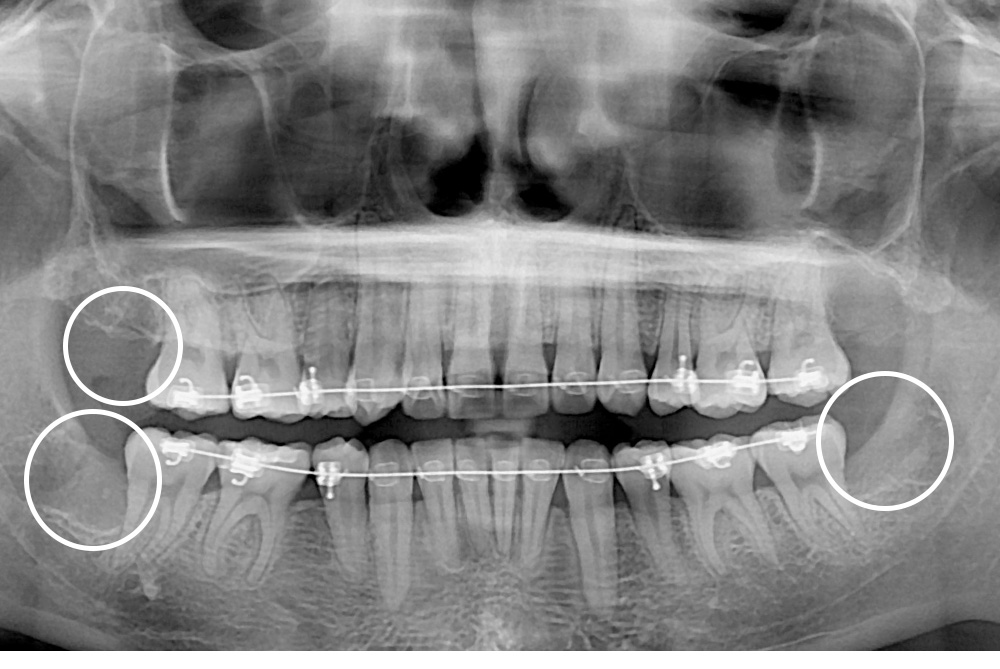

[사랑니] 매복 사랑니 발치

치료후 : 2020-08-07

세종치과는 구강악안면외과학 박사이신 원장님이 발치하는 치과입니다.